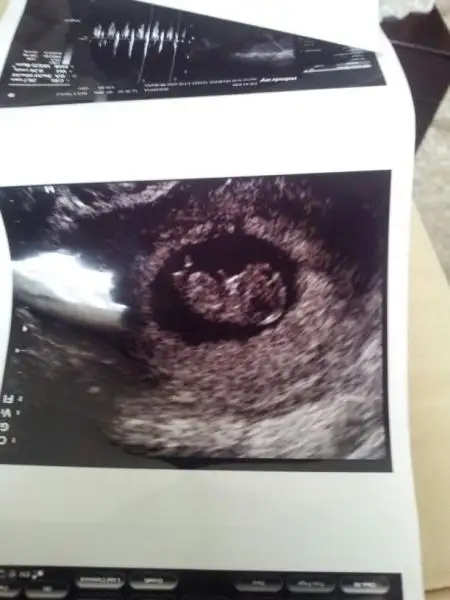

:Kizlar hepinize Merhaba ben yeniyim burda çok dikkatimi çekti ve üye oldum ben iki tane Bebeğimi kaybettim birini 10 haftalik düşürdüm diger meleğimi dogduktan 4 ay sonra kaybettim ilkinin cinsiyetini bilmiyorum ama vefat eden melegim erkekti simdi 13 haftalik tekrar hamileym inş rabbim bu bebegi bagislar bana sayfaniz dikkatimi cekti ben elbette en basta saglikli sihatli olmasi istiyorum ama kaybettigim bebegi erkek oldugu icim erkek olmasini istiyorum bende koysam usg yi yorum yapar misiniz ozellikle ORKDM RICA ETSEM COK TEŞEKKÜR EDERİM SIMDIDENEki Görüntüle 1031606 Eki Görüntüle 1031606 :